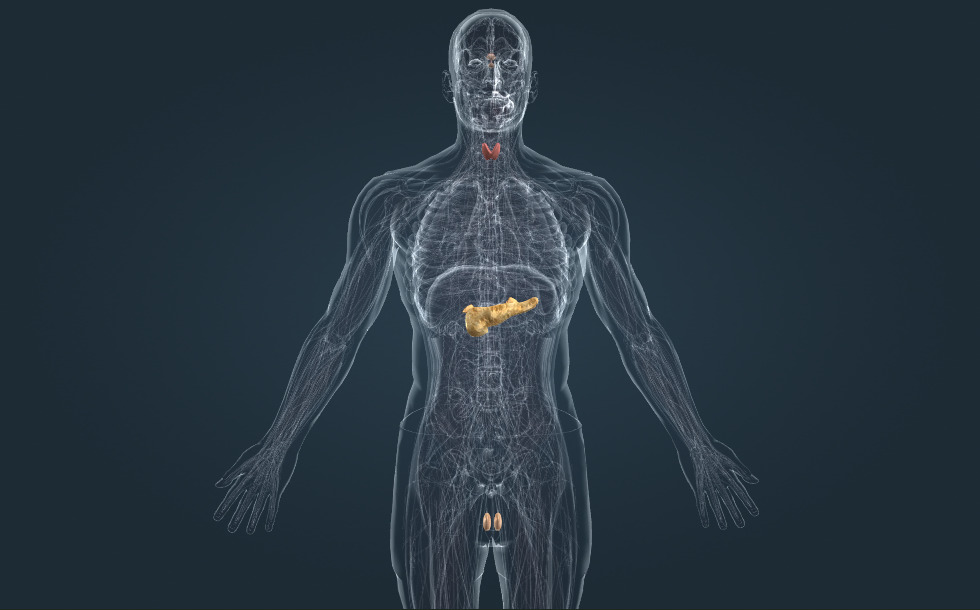

Sistema endocrino

- páncreas - Secreta insulina que reduce el nivel de glucosa en la sangre. La deficiencia de insulina causa diabetes.

- glándula tiroides - Secreta la hormona T4 (tiroxina) que aumenta la oxidación biológica. Cumple un importante papel en el desarrollo adecuado del cerebro y en el crecimiento normal. La producción excesiva de las hormonas tiroideas causa la enfermedad de Graves-Basedow, mientras que el hipotiroidismo causa bocio o cretinismo (debido al hipotiroidismo congénito).

- glándula pituitaria (hipófisis) - Constituye, junto con el hipotálamo, el eje hipotalámico-hipofisario-adrenal, el centro de nuestro sistema endocrino.

Las hormonas son producidas por las glándulas del sistema endocrino. La adrenalina es secretada por la glándula suprarrenal, la insulina por el páncreas y la tiroxina por la glándula tiroides. El centro del sistema endocrino es el eje hipotalámico-hipofisario. El hipotálamo produce hormonas regulando la glándula pituitaria que estimula la producción de otras glándulas: las glándulas tiroides, las glándulas suprarrenales y las glándulas reproductivas. El páncreas no está regulado por el eje hipotalámico-hipofisario.

Las hormonas son producidas por las glándulas del sistema endocrino. La adrenalina es secretada por la glándula suprarrenal, la insulina por el páncreas y la tiroxina por la glándula tiroides. El centro del sistema endocrino es el eje hipotalámico-hipofisario. El hipotálamo produce hormonas regulando la glándula pituitaria que estimula la producción de otras glándulas: las glándulas tiroides, las glándulas suprarrenales y las glándulas reproductivas. El páncreas no está regulado por el eje hipotalámico-hipofisario.